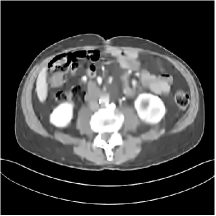

III.C.2. Simulation Framework, Reconstruction Results, and Comparisons

The synthesized low-dose clinical measurements are simulated from regular-dose images at a resolution of mm with a fan-beam CT geometry corresponding to a monoenergetic source at incident photon intensity . The sinograms are of size . The width of each detector column is mm, the source to detector distance is mm, and the source to rotation center distance is mm. We reconstruct images of size with the pixel size being mm mm.

We conducted experiments on one test slice used for parameter tuning (L067-slice 120) and four independent test slices (L109-slice 90, L192-slice90, L333-slice140, L506-slice 100) of the Mayo Clinic data. For PWLS-EP, we ran iterations using relaxed OS-LALM and set regularization parameter . We used the same as the phantom experiments for Algorithm 2. The process of selecting a general set of reconstruction parameters () for the Mayo Clinic test slices is identical to that for the XCAT phantom in Section III.B.2. The selected regularization parameter and the parameters that control the sparsity of the coefficient maps are for ST, , , , , for MARS2, , , , , , , for MARS3, , , , , , , , , , , for MARS5, and , , , , , , , , , , , , , , for MARS7, respectively.

Figs. 8, 9, 10, and 11 show the reconstructions of the four independent slices using the FBP, PWLS-EP, PWLS-ST, PWLS-MARS2, PWLS-MARS3, PWLS-MARS5, and PWLS-MARS7 schemes, respectively. Additional Mayo Clinic experimental results of the parameter tuning case (Fig. 15) are shown in the supplementary document. Table 1 lists the RMSE and SSIM values of reconstructions of the four independent test slices, with the best values bolded. Generally, the five and seven layer models provided the best RMSE and SSIM values. They outperform the single-layer model by HU in RMSE on average. However, the MARS5 and MARS7 models perform similarly. In order to strengthen the benefits of the multi-layer model, Table 2 lists the RMSE of the reconstructions in four different ROIs (shown in the reference of Fig. 11) with seven methods for slice 100 of patient L506. By observing the reconstructed images, we see that although the ST model achieves a cleaner reconstruction result than FBP and PWLS-EP, it still sacrifices some sharpness of the central region and suffers from loss of details. The deeper models have a somewhat more positive effect in terms of maintaining subtle features, which is clearly more essential to clinical diagnosis. Furthermore, as we will discuss later, after considerable parameter tuning, we found that the information contained in residual maps is gradually decreased with the number of layers, eventually vanishing at some layer, which suggests that very deep unsupervised models might not offer significantly better image quality.